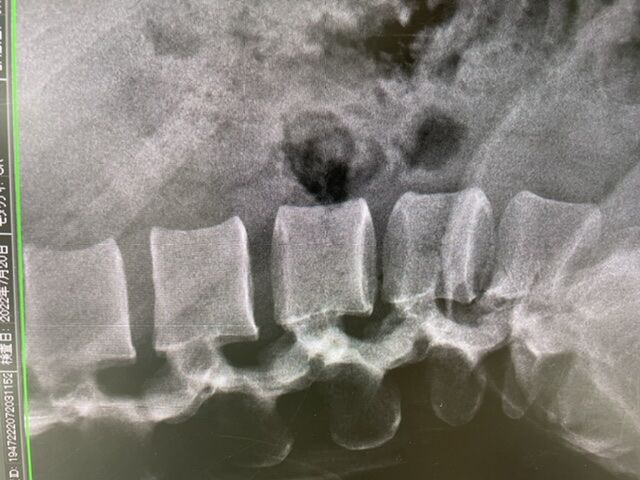

東京オリンピックまで、0.7秒およばなかった、

現在、日本ランキング4位

某大学 競泳選手 腰の悩みで来院

9C54D067-88B0-4444-8FB2-24E7C3887390

腰の筋膜が硬く、股関節、大腿部の強いタイトナスが

原因のようです、ストレッチ、筋膜リリース手技で

なおしていきます